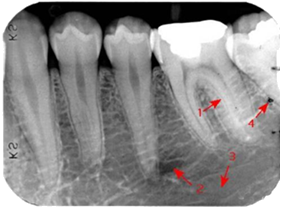

口腔执业-口腔颌面医学影像诊断学(2022)-基础学习[超值精品]